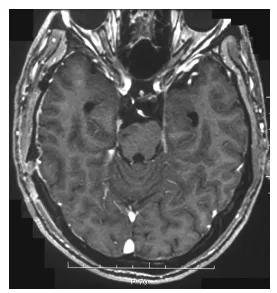

病理检查显示典型施万细胞瘤栅栏样结构,伴多处出血区及薄壁扩张血管。患者术后恢复过程顺利,偏瘫症状改善,1周后出院。术后4个月MRI检查未见肿瘤复发。

术后MRI显示肿瘤大体全切,脑干受压解除。